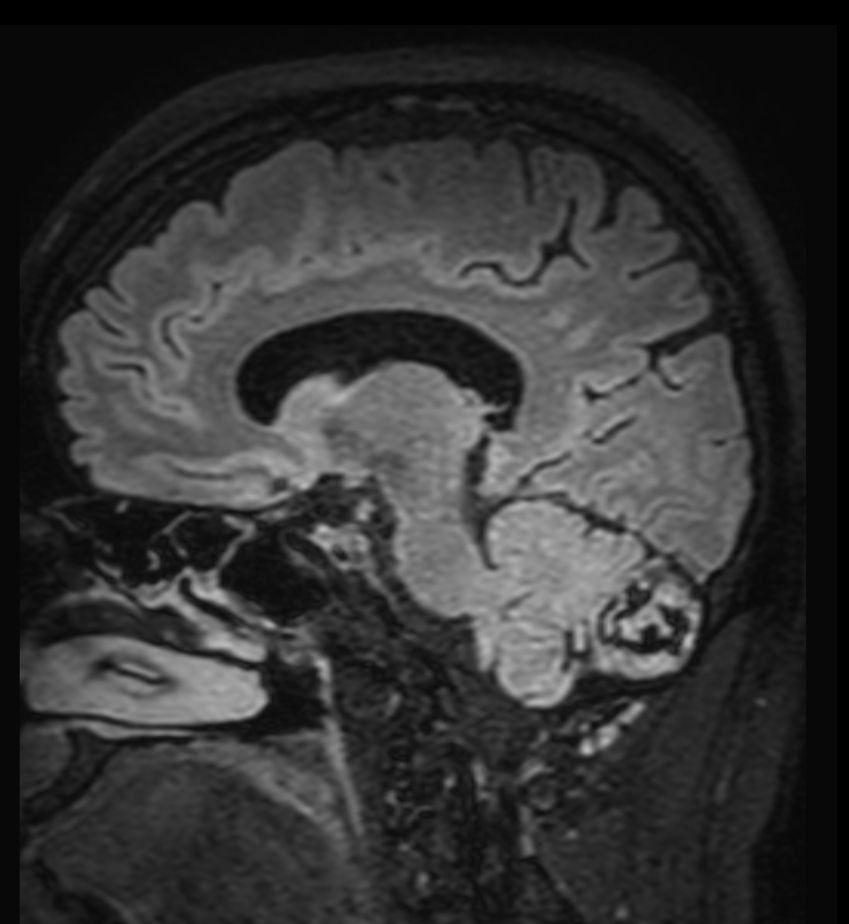

Patient with a lesion in the cerebellum. The ExamCard includes Compressed SENSE to accelerate the entire exam and techniques for motion reduced imaging (MultiVane XD), 3D imaging to acquire high resolution data in multiple directions, 3D susceptibility weighted imaging (SWIp), angiography sequences (Time-of-Flight and Contrast-Enhanced MRA with both arterial and venous phases), DTI with MultiBand SENSE to acquire a high number of diffusion directions in a short scan time and EPIC Brain to bring down any residual distortion.

T2w TSE MultiVane XD